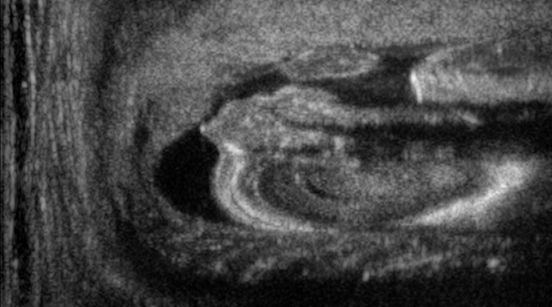

We train each learning-based network (custom-WDSR) with 1.5K images, where the input is the outcome of the selected up-sampling method (i.e., Cubic convolution), and the target is the original high-resolution image. Indeed, input and target images have the same resolution, as the reconstruction of the missing lines has been already performed by Cubic convolution. Figs. 3, 4, and 5 show the results of the network prediction, compared with the input and the target images. Target images correspond to spatial high-resolution images; input images are the outcome of the up-sampling interpolation, which is applied to spatial low-resolution images (i.e., the down-sampling along the lateral direction of high-resolution images); prediction images represent the output of the neural network.

Our framework visually improves the results, in terms of blurring and artefacts. This result is more evident in the magnification of the ear of the foetus (Fig. 3), the mitral valve (Fig. 4), and the mass edges (Fig. 5). Fig. 6 shows the error image of the three anatomical districts with both 2X and 4X up-sampling factors, with the maximum error in the scale . The error is more evident in the contours of the anatomical structures; moreover, the abdominal district shows a smaller error than the cardiac and obstetric ones. We underline that the view for each image is scaled to its maximum, to improve the visualisation of the error.